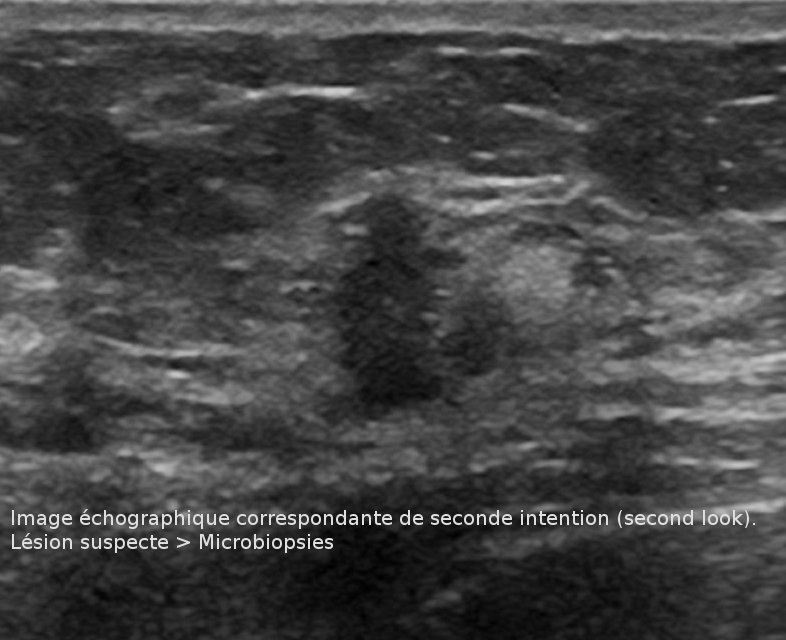

Il est réalisé toujours en deuxième intention après un examen mammographique et/ou échographique.

Une IRM du sein (ou IRM mammaire) permet donc de compléter et de préciser l'exploration de certaines

anomalies du sein détectées à la mammographie et/ou à l’échographie.

En France, les Biopsies sous IRM ne sont pas encore réalisables en pratique clinique, ce qui rend difficile l'exploitation d'un résultat IRM positif quand tous les autres examens sont négatifs! L'avenir est tourné vers la mammographie numérique de contraste qui fonctionne sur le même principe que l'IRM et permet de mettre en évidence des prises de contrastes anormales par soustraction d'images. Ces dernières peuvent alors bénéficier de prélèvements en un temps de façon aisée grâce au système classique de repérage stéréotaxique.